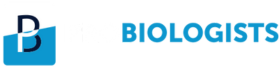

Tuberculosis of the appendix is a rare finding despite the high frequency of intestinal tuberculosis. Even in areas where tuberculosis is common, it is difficult to make the right diagnosis because of the clinical picture mimicking acute appendicitis, when there are no definitive signs of any system infected with tuberculosis [1]. A 37-year-old female presented with severe pain in the right iliac fossa. On clinical examination, she had fever and tachycardia with guarding and rigidity in the right iliac fossa. The patient underwent contrast-enhanced computed tomography (CT) scan of the abdomen, which revealed a distended retrocaecal appendix with thick enhancing walls (arrow in Figure 1A) and adjacent fat stranding. Incidentally, thickening of the uterine cervix was noted, for which she underwent magnetic resonance imaging (MRI) evaluation. The MRI depicted findings of chronic cervicitis and helped to confirm appendicitis (arrow in Figure 1B). There was gross effusion also noted in the right pleural cavity (star in Figure 1B).

The patient underwent appendicectomy and a reddish swollen angry-looking appendix was found intra-operatively (arrow in Figure 1C). The patient had uncomplicated post-operative period.

On histopathology, there were multiple granulomatous lesions and areas of caseous necrosis surrounded by Langerhan’s giant cells and epithelioid cells (arrow in Figure 1D). The patient started on anti-tubercular drugs and kept on follow-up. She is doing fine till the last follow up. Patients present with vague clinical symptoms in gastrointestinal TB. Severe abdominal pain, weight loss, intermittent constipation and diarrhoea associated with worsening of the pain [2]. Acute tubercular appendicitis being a very rare condition, a contrast-enhanced CT scan is the ideal imaging modality for the evaluation of such cases.

Figure 1. A. Axial section of contrast-enhanced CT scan shows distended retro-caecal appendix, measuring 10 mm in diameter with adjacent fat stranding. B. Coronal T2 weighted MR image shows inflamed appendix in the right paracolic gutter. C. Intra-operative image shows distended appendix having a reddish serosa. D. Histopathology image show caseous necrosis and infiltration of the Langerhan’s giant cells and epithelioid cells.